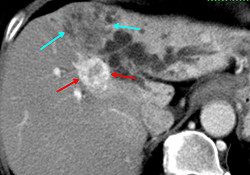

肝細胞癌と肝内胆管癌の混合症例を提示します。図1では、青矢印のやや黒く写るところが肝内胆管癌で、赤矢印の白く写るところが肝細胞癌です。造影剤注入後に早いタイミングで撮影することによって腫瘍の鑑別がしやすくなります。図2は同じ症例の3D画像です。血管構築像を3D作成することによって腫瘍と血管の位置が明確になり、手術の際に役に立ちます。図3は膵臓に沿って断面の傾きを調整した画像(多方向断面)で、膵臓中央部に腫瘍(小矢印に囲まれた部位)があり、腫瘍によって閉塞した膵管(大矢印)が拡張している様子が観察されます。